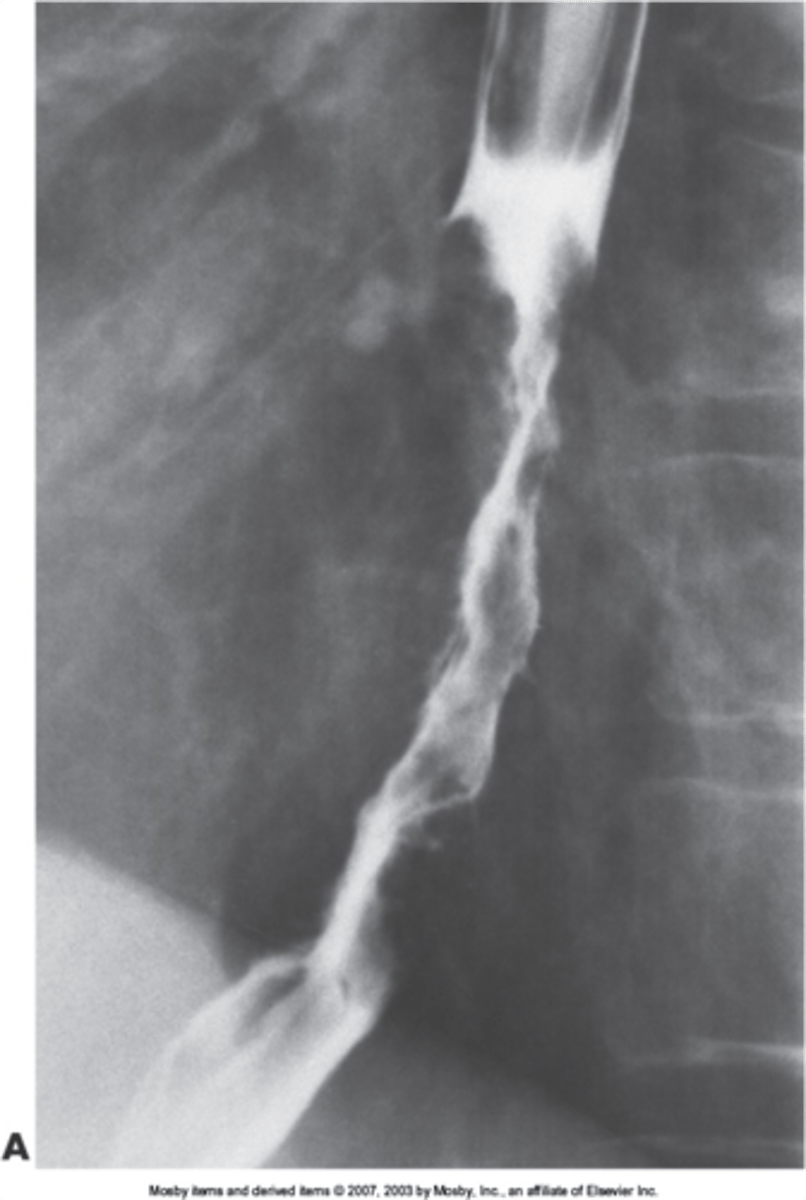

esophageal strictures

narrowing of the esophagus

superior- scarring from suicide attempts, lye or corrosive material swallowed, smooth appearance

middle and inferior- scarring from GERD, neoplasm

esophageal carcinoma

irregular column of barium entering stomach with peak like projections of barium -> concerning for malignancy